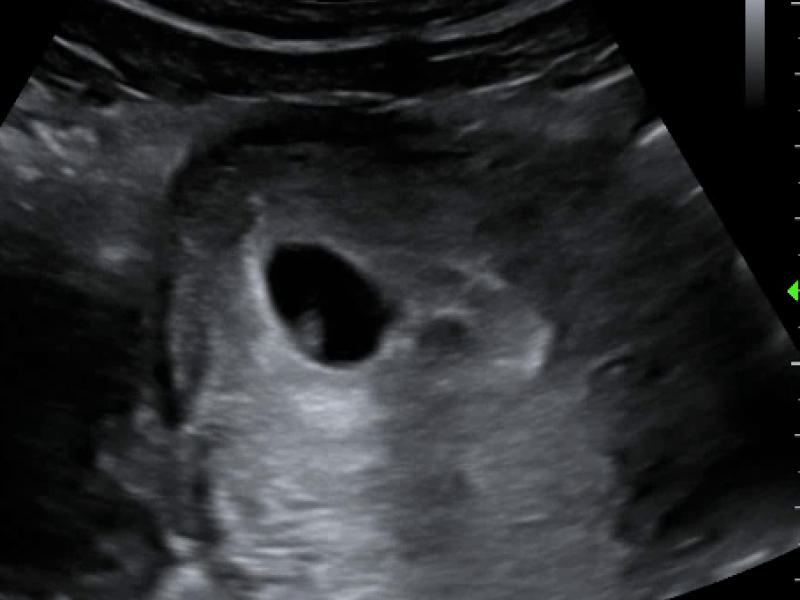

Left: Trans-abdominal curvilinear probe Right: Trans